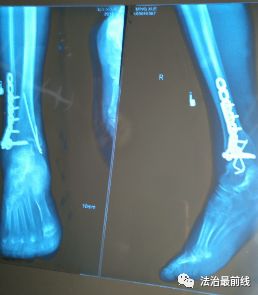

2018年8月28日上午,李女士被推进手术室。手术后,李女士脚踝的右内踝和右外踝处分别留下了约7厘米和11厘米的手术切口,并使用了螺钉、钢板等内固定物。

在家人的建议下,李女士先后到重庆市南川区南坪卫生院、綦江县人民医院复查,两家医疗机构给出的结果都一样:有螺钉放错了位置。

李女士告诉记者:“这两家医院的医生都说,是螺钉打到关节里面去了,还有这两个眼不该钻的,骨头那两个眼,不该钻的都钻出来了。”

提交申请后,李女士立即转院到广西骨伤医院进行治疗。广西骨伤医院提供的入院记录显示:“腓骨远端可见两枚螺钉穿入右踝关节面”且“术口感染”“钢板外露”。医生说,“两枚穿入踝关节的螺钉”是李女士病情恶化的主要原因。

鉴定书认为,患者术后出现伤口感染及不愈合的原因,一是损伤程度,二是手术时机选择欠妥,三是医方手术失误,将右外踝远端两枚螺钉置入关节内,造成患者目前右踝关节创伤性关节炎、关节僵硬、关节功能严重障碍、右侧内外踝骨折延迟愈合。南宁市医学会认为,“此病例属于三级乙等医疗事故,医院方承担主要责任”。

院方对鉴定结果中的“手术时机选择欠妥”、以及“内固定螺钉进入关节腔”存疑。院方认为,“可确认当时并无螺钉进入关节腔”、“术后影像学诊断仅作为参考,术后外院取出螺钉也并无法确认螺钉是进入了关节腔”。

滕某承认,出于手术需要,确实将两枚螺钉打入了李女士的关节内。这一说法与医院方提交的《医疗事故再次鉴定申请书》第3点“有明显出入”,这到底是怎么回事呢?